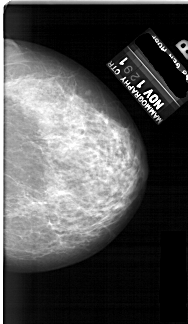

A_1691_1.LEFT_MLO

LEFT_MLO LINES 6466 PIXELS_PER_LINE 4126 BITS_PER_PIXEL 12 RESOLUTION 43.5 OVERLAY